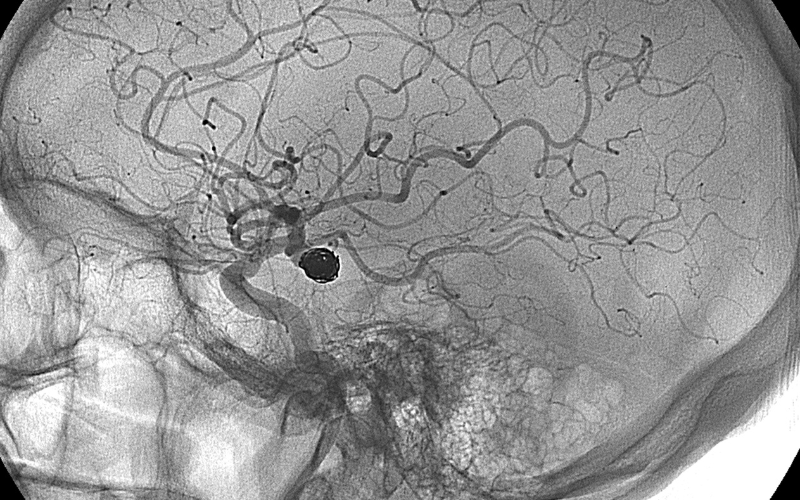

Aneurysm